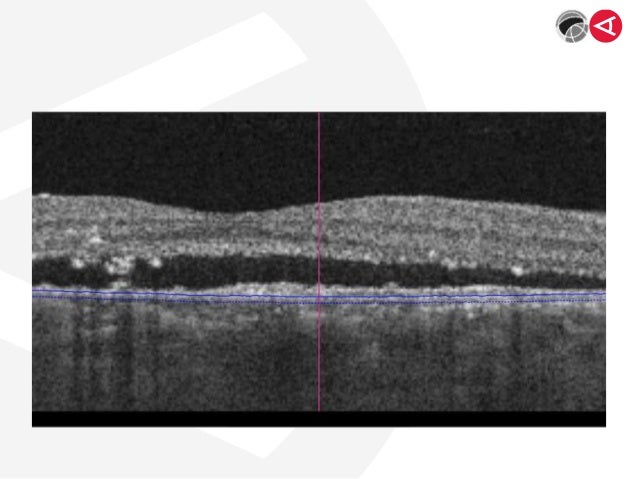

Morphologische Charakteristika Der Myopen Choroidalen Neovaskularisation Springermedizin De